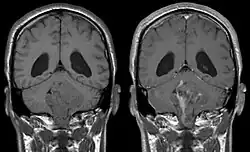

An ependymoma is a tumor that arises from the ependyma, a tissue of the central nervous system. Usually, in pediatric cases the location is intracranial, while in adults it is spinal. The common location of intracranial ependymomas is the floor of the fourth ventricle. Rarely, ependymomas can occur in the pelvic cavity.

Ependymomas make up about 5% of adult intracranial gliomas and up to 10% of childhood tumors of the central nervous system (CNS). Their occurrence seems to peak at age 5 years and then again at age 35. They develop from cells that line both the hollow cavities of the brain and the central canal containing the spinal cord, but they usually arise from the floor of the fourth ventricle, situated in the lower back portion of the brain, where they may produce headache, nausea and vomiting by obstructing the flow of cerebrospinal fluid. This obstruction may also cause hydrocephalus. They may also arise in the spinal cord, conus medullaris and supratentorial locations.[7] Other symptoms can include (but are not limited to): loss of appetite, difficulty sleeping, temporary inability to distinguish colors, uncontrollable twitching, seeing vertical or horizontal lines when in bright light, and temporary memory loss. It should be remembered that these symptoms also are prevalent in many other illnesses not associated with ependymoma.

Ependymomas are classified by their location, cellular features, and more recently, molecular characteristics. The three locations are defined as supratentorial, posterior fossa (also referred to as infratentorial), and spinal.[13] They are classified as Grade I, Grade II, or Grade III. Within the last decade, ependymomas have been further characterized by 10 molecular subtypes.[14] Ependymoma tumor location, grade, and molecular features determine the treatment plan and prognosis.

Intracranial ependymomas, including supratentorial and posterior fossa, make up 90% of ependymomas in children. The supratentorial region is the upper brain region, or cerebrum, and contains the lateral and third ventricles. The posterior fossa, or infratentorial, is behind or below this region in the area of the brainstem and cerebellum and contains the fourth ventricle. A majority of intracranial pediatric ependymomas are in the posterior fossa.[15] Patients with intracranial ependymomas typically present with increased intracranial pressure that results in headaches, dizziness, nausea, and vomiting. The third location of ependymomas is within the central canal of the spinal cord. Spinal ependymomas comprise about 65% of adult ependymomas and most often occur in the lumbosacral region.[13] Patients with spinal ependymomas can present with back pain, numbness or weakness in the limbs, and urinary or bowel problems.